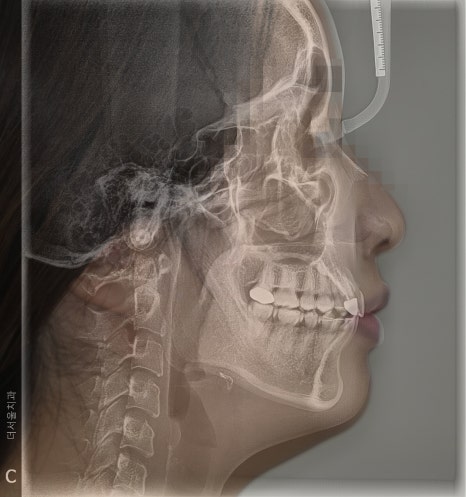

측면에서 바라보면

송곳니가 튀어나온게 두드러졌으며

치열이 고르지 못하고

삐뚤빼뚤 한 것을 볼 수 있었습니다.

정리해 보면

- 12번 [측절치] = 왜소치